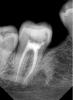

DcNext Опубликовано 5 мая, 2011 Поделиться Опубликовано 5 мая, 2011 лечили пульпит 47,по апекслокатору 0,5 до верхушки, по снимку....не очень Ссылка на комментарий

DcNext Опубликовано 6 мая, 2011 Автор Поделиться Опубликовано 6 мая, 2011 локатор от эндомотора морита,латералил,но правда не очень по снимку...меня больше интерисует почему так до фига до ренгенологической верхушки,каналы конечно склерозированы сильно,08 поначалу только на 18-19 ммпроходил,а апекслокатор пищал на 21мм Ссылка на комментарий

DcNext Опубликовано 7 мая, 2011 Автор Поделиться Опубликовано 7 мая, 2011 пломбировал гуттой с AH+,прошло 2 дня ничего не беспокоит...может не надо раздалбывать апекс ради картинки... Ссылка на комментарий